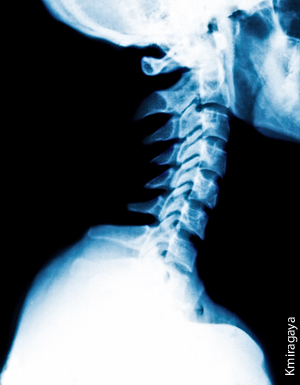

The atlas bone, or C1, is a two-ounce, doughnut-shaped bone that is the very first vertebrae of your spine.  It is just under the back of your head and holds your head up, hence the name “Atlas,” who in Greek mythology held up the world on his shoulders.  The whole neck area is called the Cervical Spine and is composed of the first seven vertebrae below your head.

The atlas is called C1 and the next vertebra is called the “Axis” or C2.  Part of the brain called the “brain stem” goes down through the opening in the atlas and is completely encircled by it.  The brain stem becomes the spinal cord that continues down through openings in the vertebrae.

For proper nerve flow, the atlas must be level and positioned exactly perpendicular to the spine.  Therefore, three-dimensional x-rays are taken to determine the exact way that the atlas is out of position for each person.  Correction can be done by hand or by a sophisticated instrument developed by Dr. Roy W. Sweat, D.C., which delivers a specific, precise sound wave to the side of the neck which “pushes” the atlas into the corrected position, allowing a free flow of nerve impulses to begin to flow down through the spinal cord.